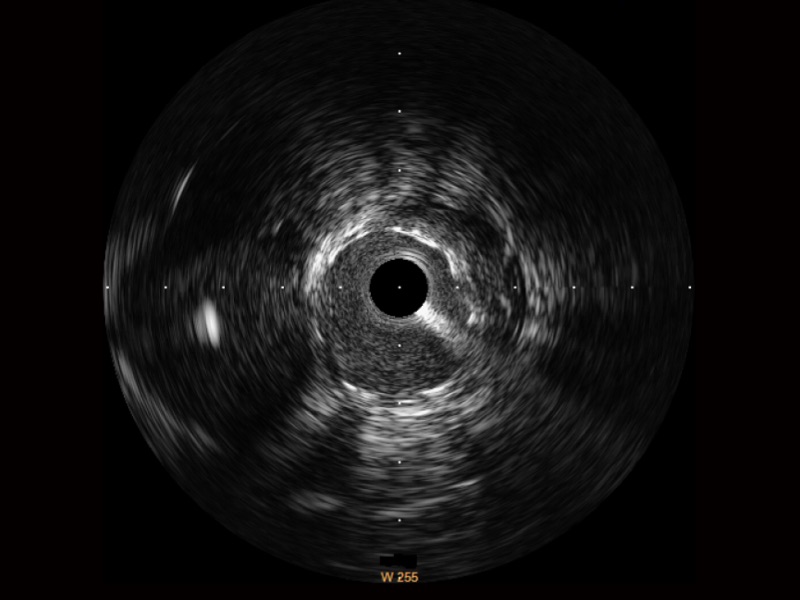

• 传统IVUS图像

对比传统IVUS导管成像,美狮贵宾会官网宽频IVUS图像的近场支架梁显影更细腻,远场中膜外血管仍清晰可辨,兼顾远中近,兼顾分辨力与穿透深度

临床图

远场分支血管及导丝

支架内血栓

组织脱垂